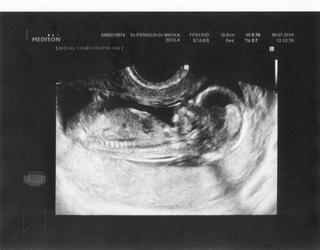

Ovsem me bavi, jak ty potvurky nemaji rady utz, takze jim "skacou". Proste si ho zamerili...a sup, byl v jinym konci delohy 🙂 (oni, protoze tam byl dr. plus vim ja, jestli medik nebo cerstvy mudr., ale ucil se, vysvetloval mu, co kde jak je videt, ev. jak nastelovat, aby videl 🙂)

opravdu je kouzelné jak to malé před doktorem prchá a všemožně se mu snaží vyšetření znemožnit...ale zážitek je to krásný když na vás tahkle z bříška zamává ..mě vždycky tečou slzy jen si na to vzpomenu 🙂